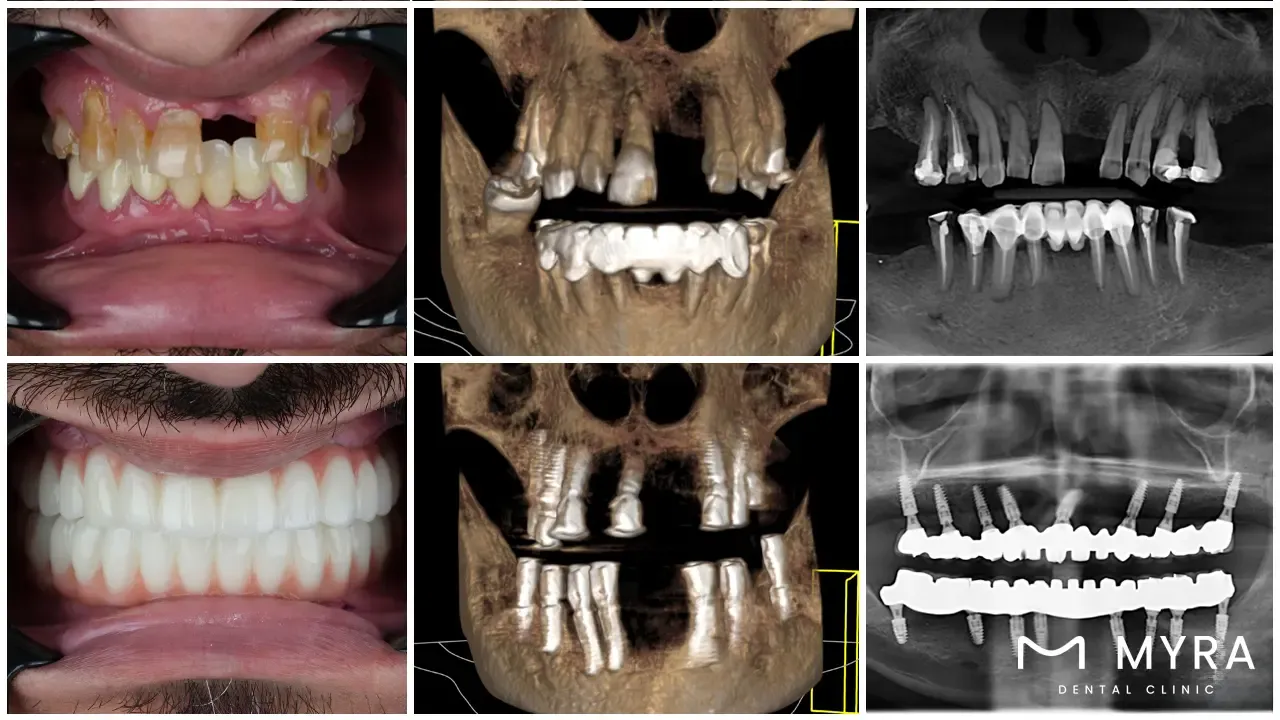

Four dental implants that act as anchors for an entire arch of replacement teeth are placed in the jawbone during the course of the procedure of all-on-4 dental implants. The all-on-4 procedure aims to offer patients a less invasive, secure, and long-lasting replacement for lost teeth than conventional implants and dentures. All-on-4 dental implants are a well-liked and modern choice for those missing a whole arch of teeth.

Patients who are missing teeth or are on the verge of losing their teeth have their dental function restored with just four dental implants by utilizing the all-on-4 dental implant treatment. The technology was developed by Nobel Biocare. People who have already lost teeth or are on the verge of losing teeth are candidates for the procedure. The company known as Nobel Biocare was the one that developed the method. Four dental implants are placed in the jawbone at key locations in accordance with the procedure as part of the All-on-4 dental implant treatment, in which a full dental arch is supported. The procedure is frequently referred to as "teeth in a day" by its patients. The strategy is the one that is helpful to the situation.

The All-on-4 dental implant procedure comprises the placement of a total of four implants into the jaw in order to provide support for a whole arch of teeth. The technique was developed by Nobel Biocare. The procedure is carried out by a dentist. It is possible to get excellent bone contact and stability with implants by angling them in the bone. The replacement teeth are constructed on a sturdy and long-lasting foundation as a consequence, which enables them to last for an exceptionally extended amount of time.

Osseointegration is the process that takes place after the dental implants have been surgically placed into the jawbone. The implants are allowed the time necessary to heal and integrate with the jawbone during the course of the procedure. The replacement teeth are affixed to the implants following completion of the procedure, which takes up to a few months on average. It necessitates a number of visits to the dentist. People who have lost teeth as a result of oral health difficulties such as an accident, tooth decay, or periodontal disease benefit from the All-on-4 dental implant techniques.

The All-on-4 dental implant procedure is divided into several stages, beginning with the first consultation and evaluation of the patient's oral health. Four dental implants are placed into the jawbone during the procedure; a temporary bridge is then attached during the first healing stage. The final bridge is installed to provide a durable and natural-looking treatment for full arch dental repair following the healing period. The patient receives comprehensive instructions on how to take care of their dental implants and maintain good oral hygiene during the procedure.